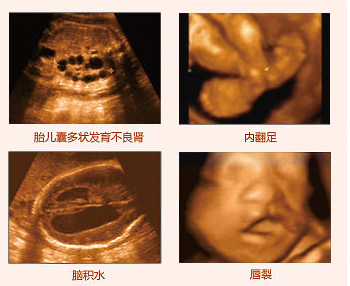

四維彩超排畸圖片

一般而言,四維彩超可篩查以下項(xiàng)目:

(2)胎兒面部畸形:如唇腭裂等;

(3)神經(jīng)系統(tǒng):無(wú)腦兒、腦積水、小頭畸形、脊柱裂及腦脊膜膨出;

(4)泌尿系統(tǒng):腎積水、多囊腎及巨膀胱、尿道梗阻;

(5)消化系統(tǒng):臍部腸膨出、內(nèi)臟外翻、腸道閉鎖及巨結(jié)腸等;

(6)其它畸形:短肢畸形,聯(lián)體畸形等;